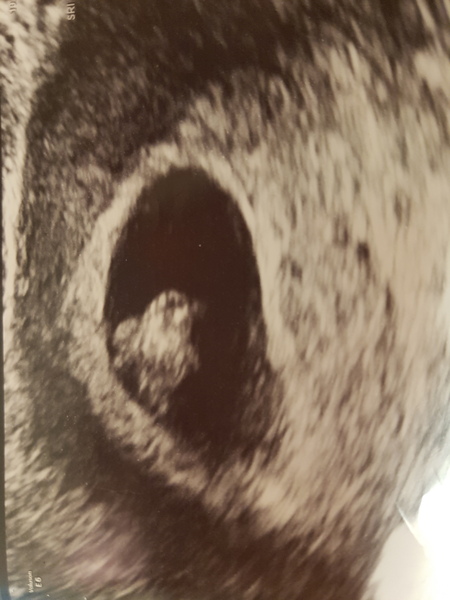

In other news I had an 8 week scan (follow up to my obligatory 6 week scan because of previous ectopic) and the sonographer was very happy with it. Now don't need to go back till 12 weeks. Really strong heartbeat and wriggling around. Pic attached. Seems like this one may actually stick and I am starting to believe it may be fourth time lucky!

ALRM lovely scan photo

@ALRM lovely scan! Whoop whoop!

Great news @ALRM scan looks great!